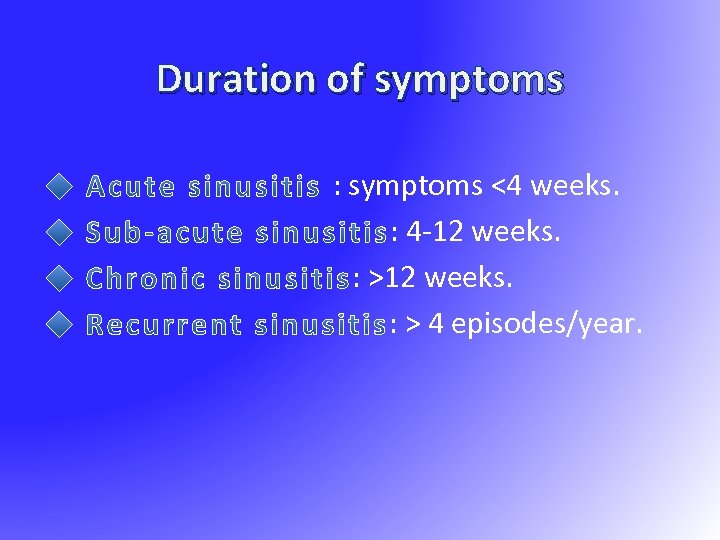

Duration of symptoms : symptoms <4 weeks. : 4 -12 weeks. : > 4 episodes/year.

Duration of symptoms : symptoms <4 weeks. : 4 -12 weeks. : > 4 episodes/year.